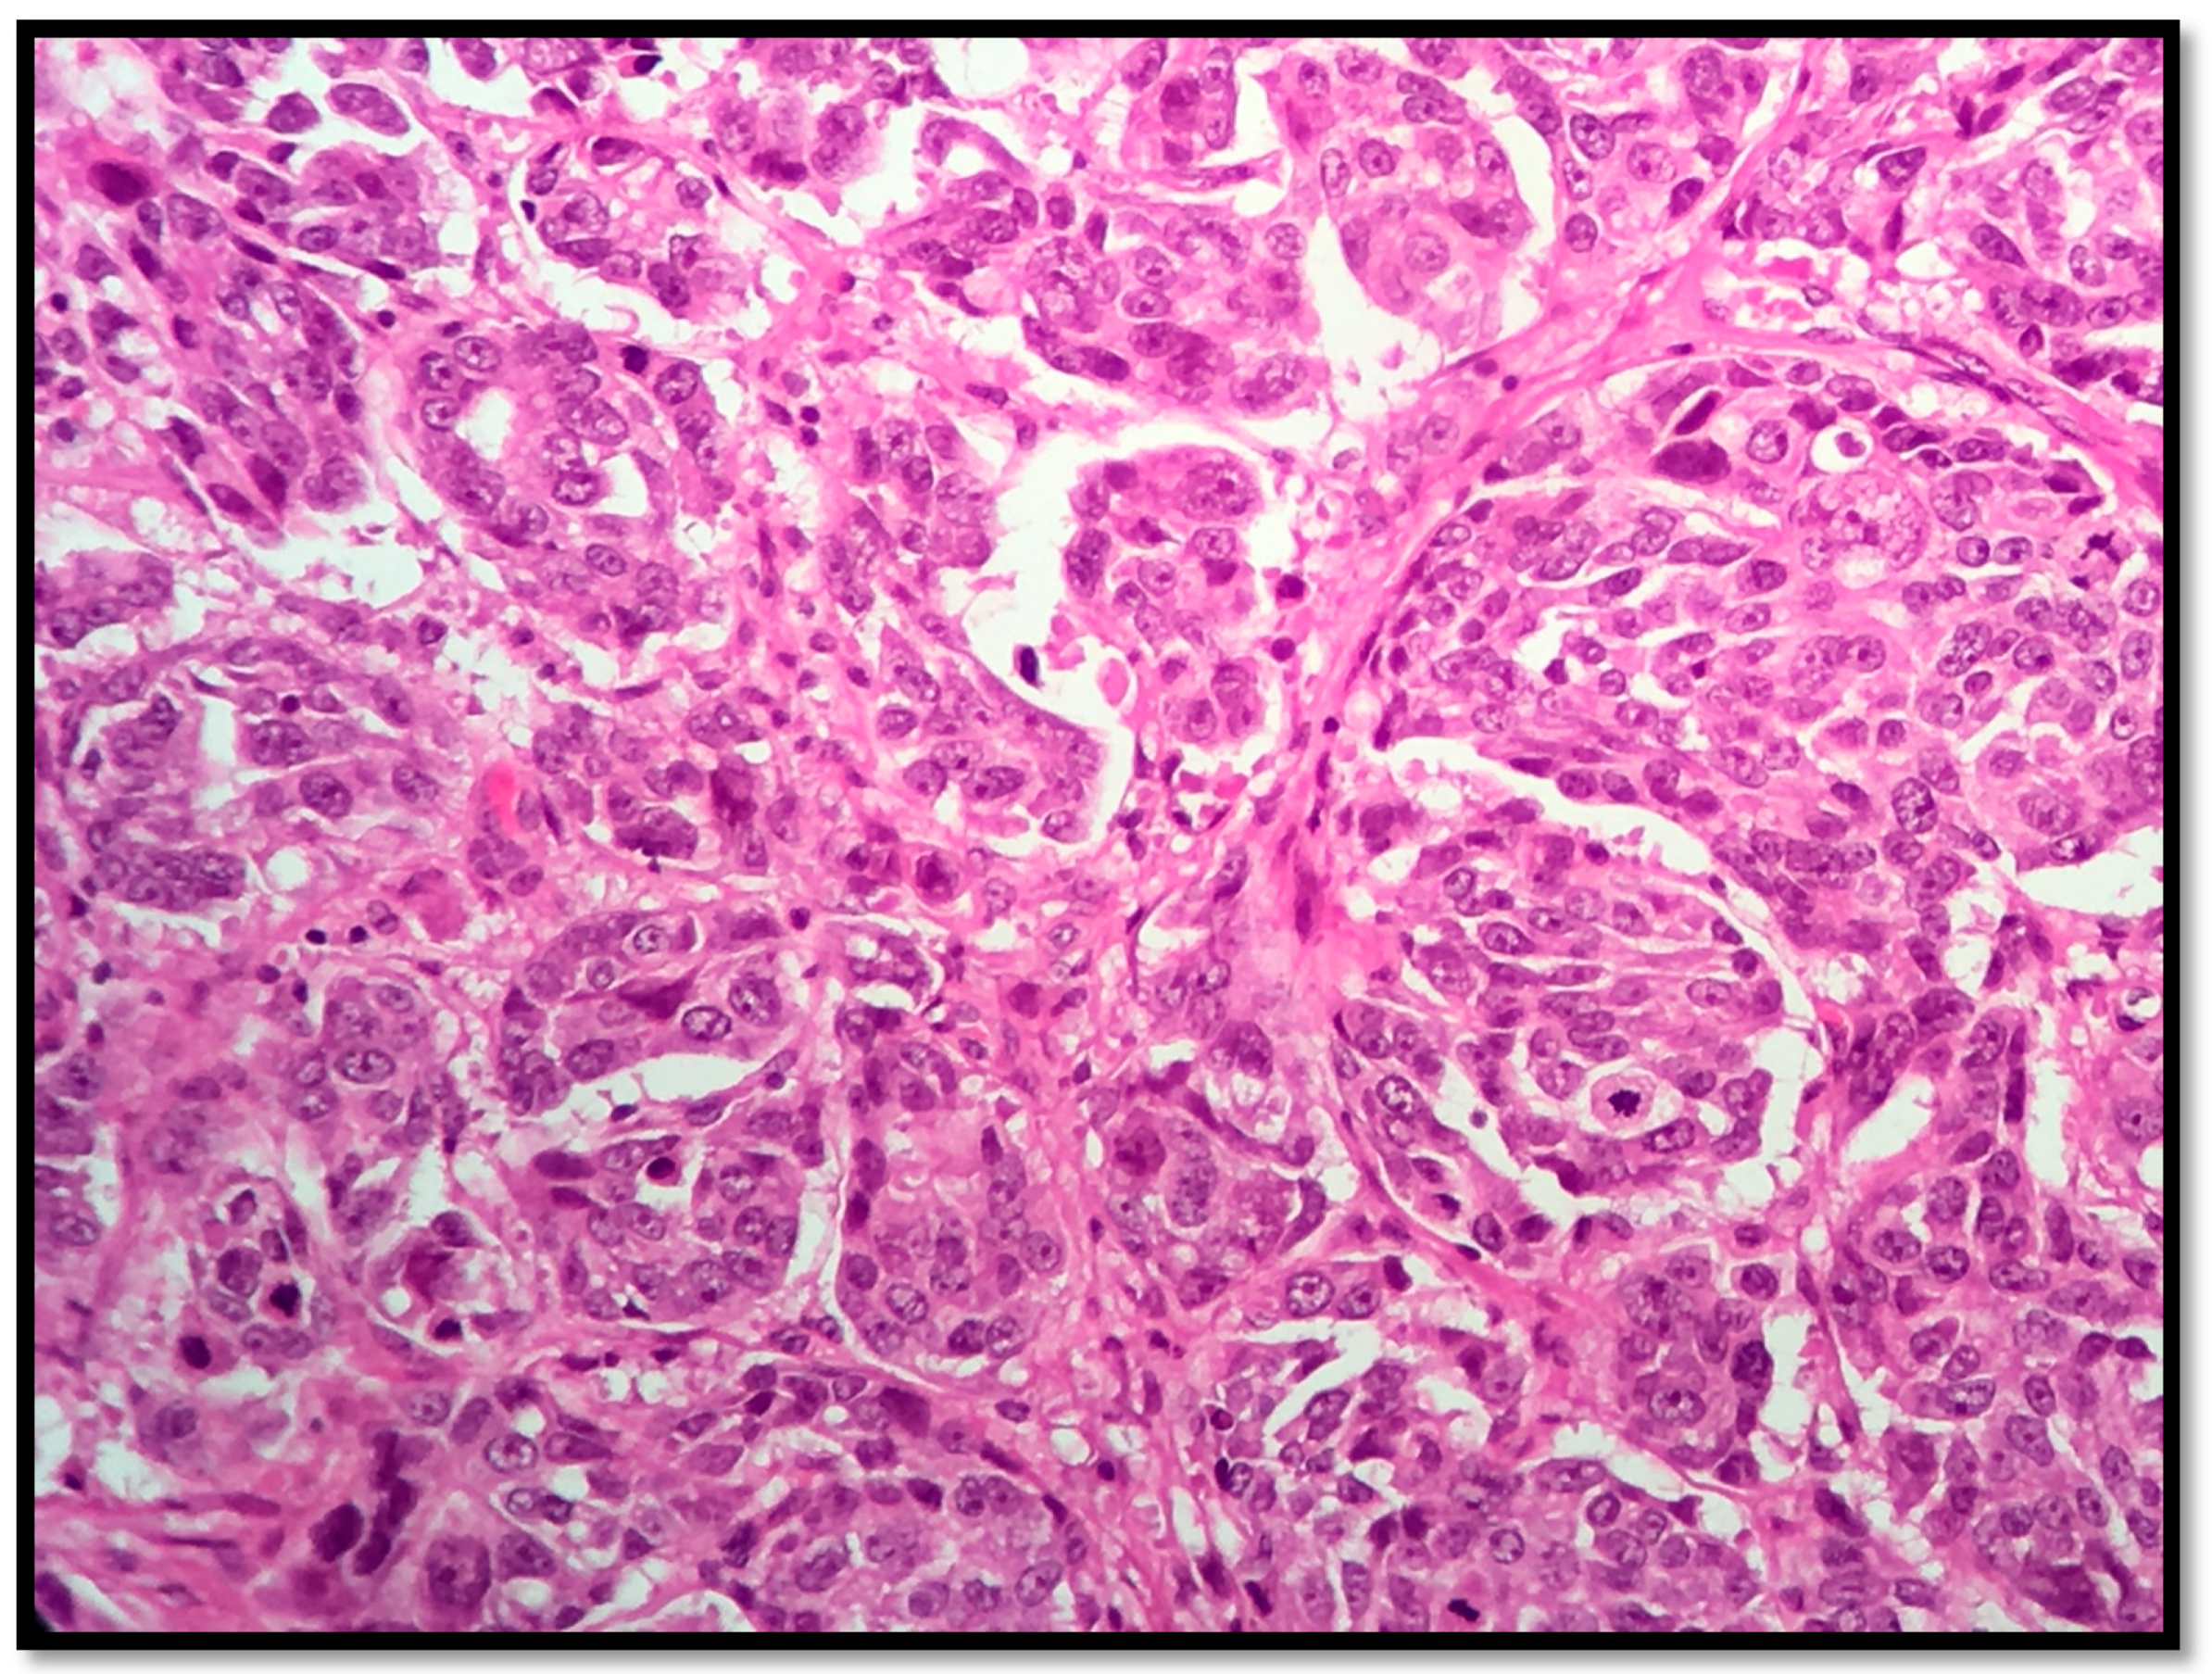

2.1. AR Assessment

2.2. Her2 Neu, ER and PR Assessment